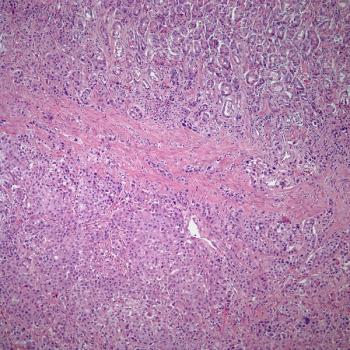

A 68-year-old woman presents with presents with a mass in the tail of the pancreas. What is your diagnosis?